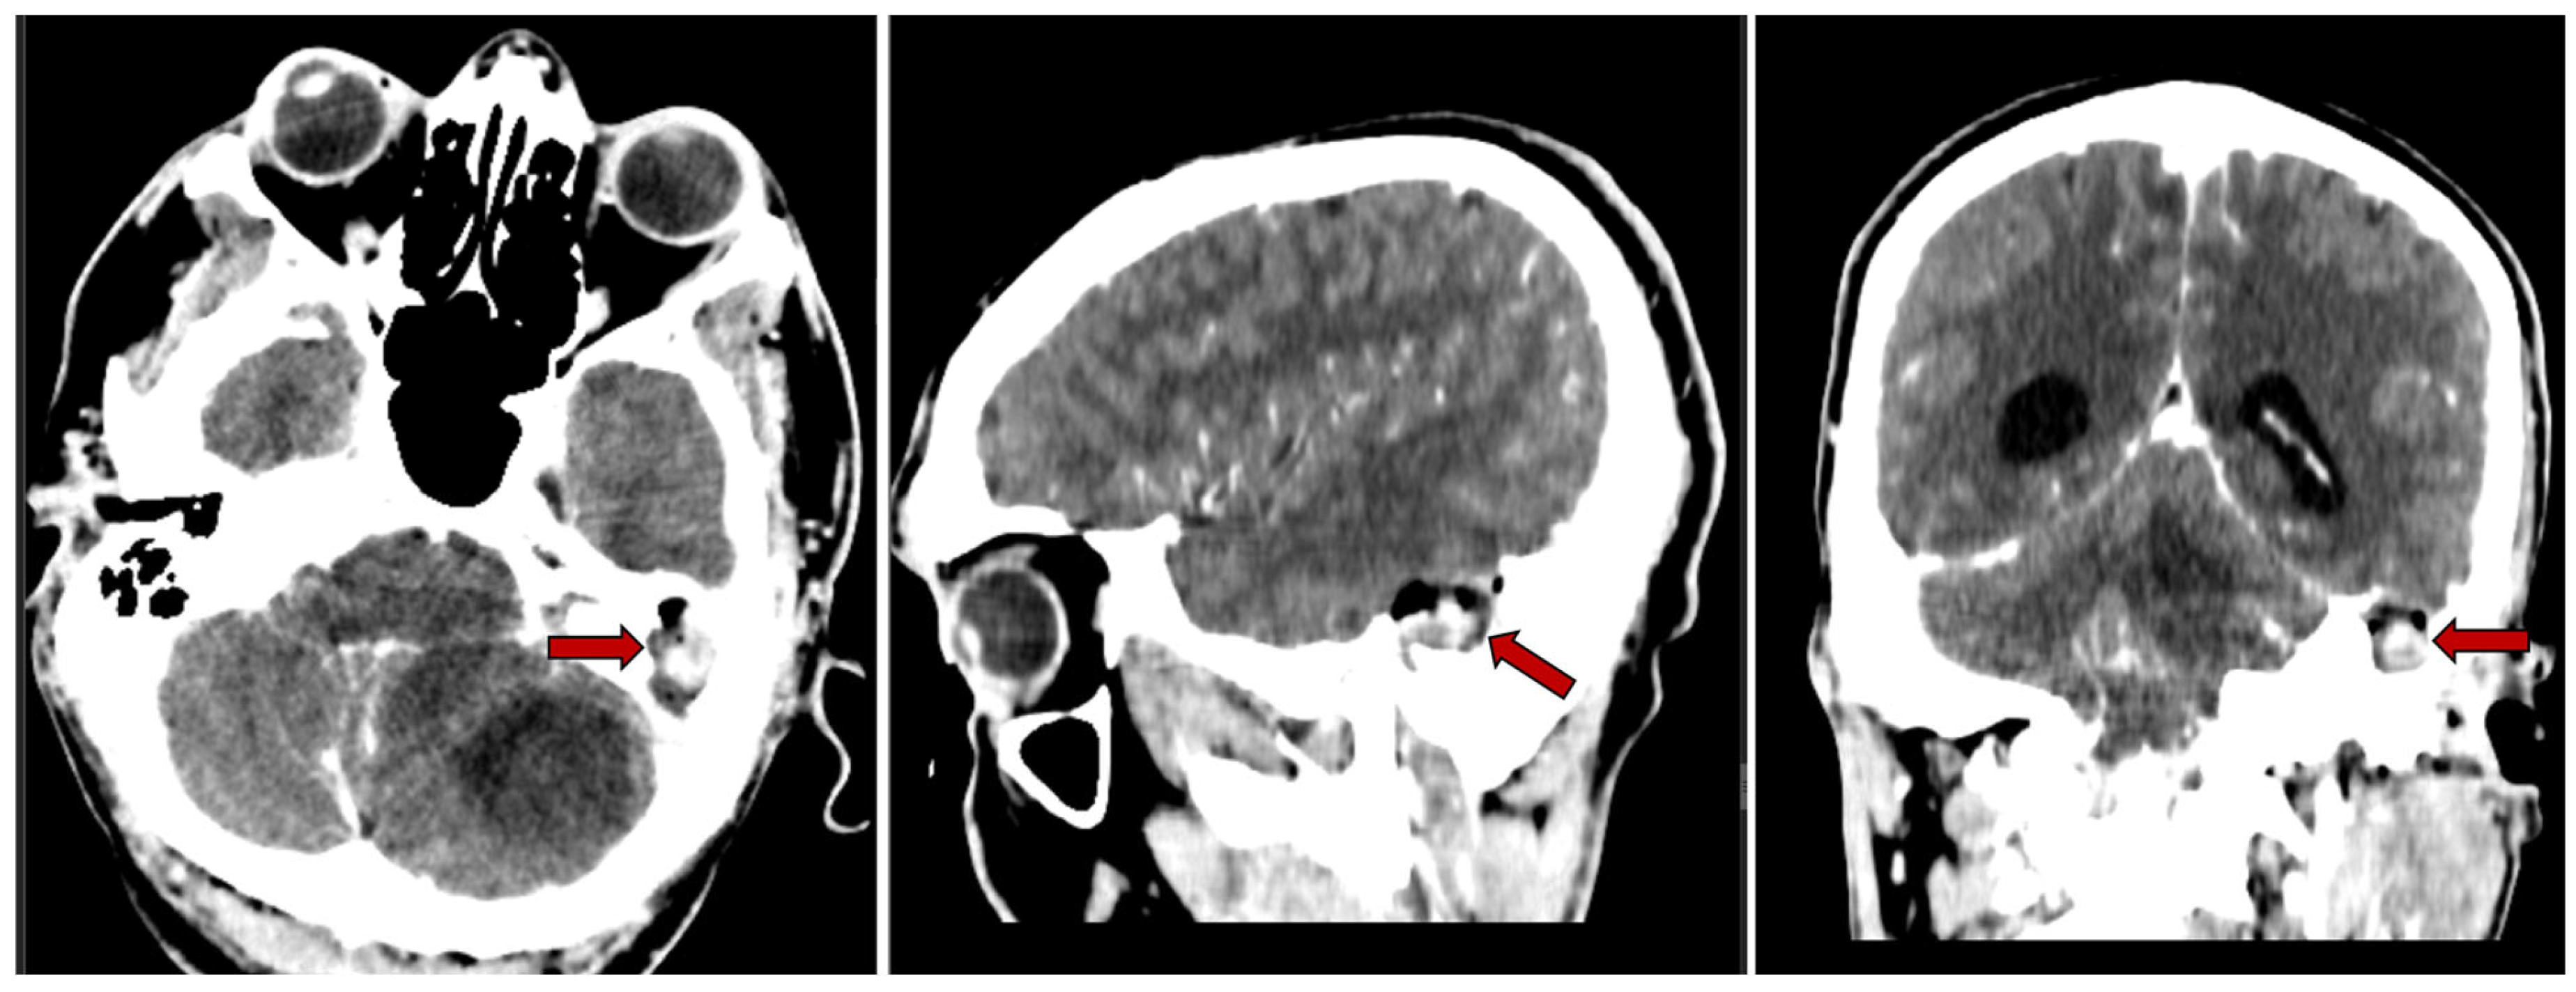

Furthermore, the contrast-enhanced CT scan revealed a left cholesteatomatous otomastoiditis (Figure 2).

Figure 2. Contrast-enhanced CT scan (axial, sagittal and coronal planes) showing a left cholesteatomatous otomastoiditis (red arrow).